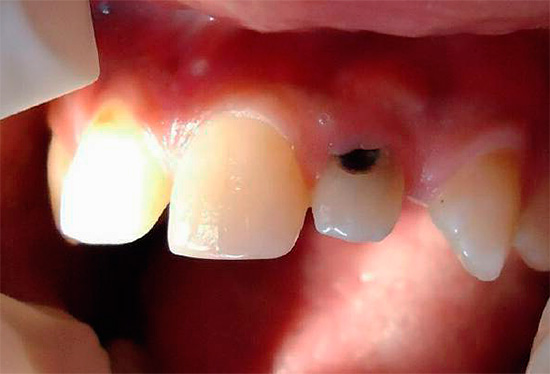

A foto abaixo mostra um exemplo típico de cárie cervical nos dentes da frente:

Ao mesmo tempo, surgem muitas perguntas sobre as causas de tais problemas e, é claro, sobre possíveis métodos para eliminar a cárie cervical, que discutiremos mais adiante.

Cervical cárie dos dentes anteriores freqüentemente causa dor ao inalar ar frio.